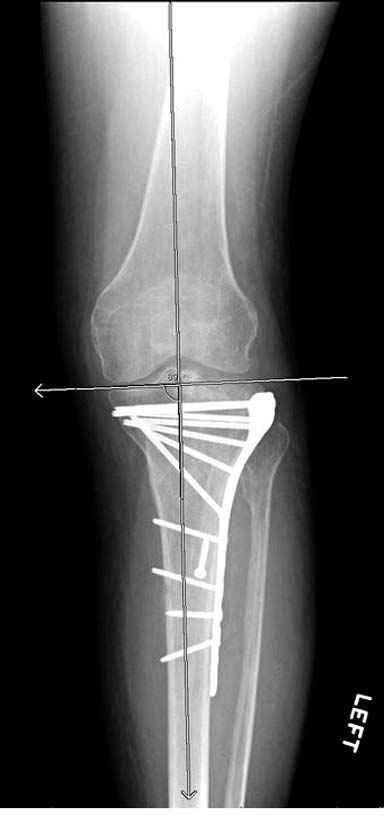

А нет ощущения, что плато "завалено" на варус?

293.jpg

21KB (22230 bytes)

Только вот линией вы вальгус показываете (норма)

Решили выполнить остеосинтез штифтом и внутрисуставного перелома пластиной и винтами. Жду мнения! Зачем мне оправдываться-я же не преступник. Диалогом называется...

Отдельные переломы тибиал плато и перелом проксимальной трети большеберцовой кости отличаются от переломов тибиал плато с вовлечением диафиза. Здесь перелом тибиал плато типа Schatzker VI, полученный в результате высокоэнергетической травмы. Перелом метафиза образовал отрыв суставной поверхности от диафиза с вовлечением медиального и латерального мыщелков. Двухмыщелковые переломы из-за укрочения опасны развитием компартаментального синдрома, повреждением латерального мениска и связок.

Если там действительная импрессия, пустое место без структуральных заполнителей, кость или синтетические материалы, не восстановится, а образуется коллапс, и ось конечности поведет после нагрузки. Кроме того там возможно "болт стяжка"?, в медиальной стороне выступает за кортекс, можно было укоротить! Потом создается впечатление, что не соответствуют мыщелки большеберцовой и бедренной костей? Покажите снимок.

Я думаю, что если с новыми, услышанными, например, от экспертов форума, оценками и размышлениями Вы вернётесь к изучению представленной Вами рентгенограммы, то увидите, что вы не восстановили ни плато, ни правильные осевые взаимоотношения. Вы оперировали на отёке, не в оптимальное время. Используя болты-стяжки, вы устроили то, что зачастую называют «костный сэндвич», такое сдавление кости много-много хуже для биологии, чем аккуратно введённая малоинвазивная вторая небольшая пластина с медиальной стороны. К тому же, и это чрезвычайно важно – ни пластина, ни заглублённый гвоздь не предотвращают здесь возможности развития вторичного варусного коллапса плато. А в условиях недостаточности опоры для медиальной суставной поверхности и латерально – ввиду отказа от пластики и отсутствия «рафтинга», слишком уж много «критических точек» нужно пройти данному пациенту. Я не знаю, куда это смотрят концы болтов стяжек? Или это гайки лежат внутрикостно? И прочая, прочая, прочая, что уже, впрочем, отмечено экспертами форума.